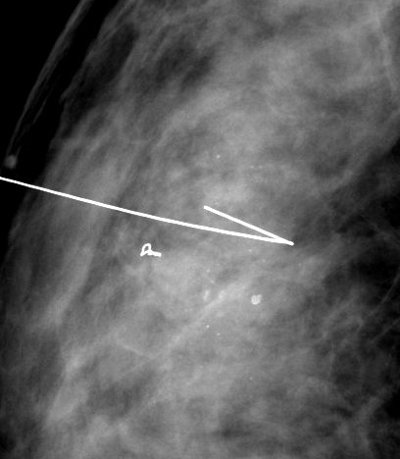

Mammotome biopsies du sein

nous sommes également là pour la prise en charge des actes interventionelles sur le sein.